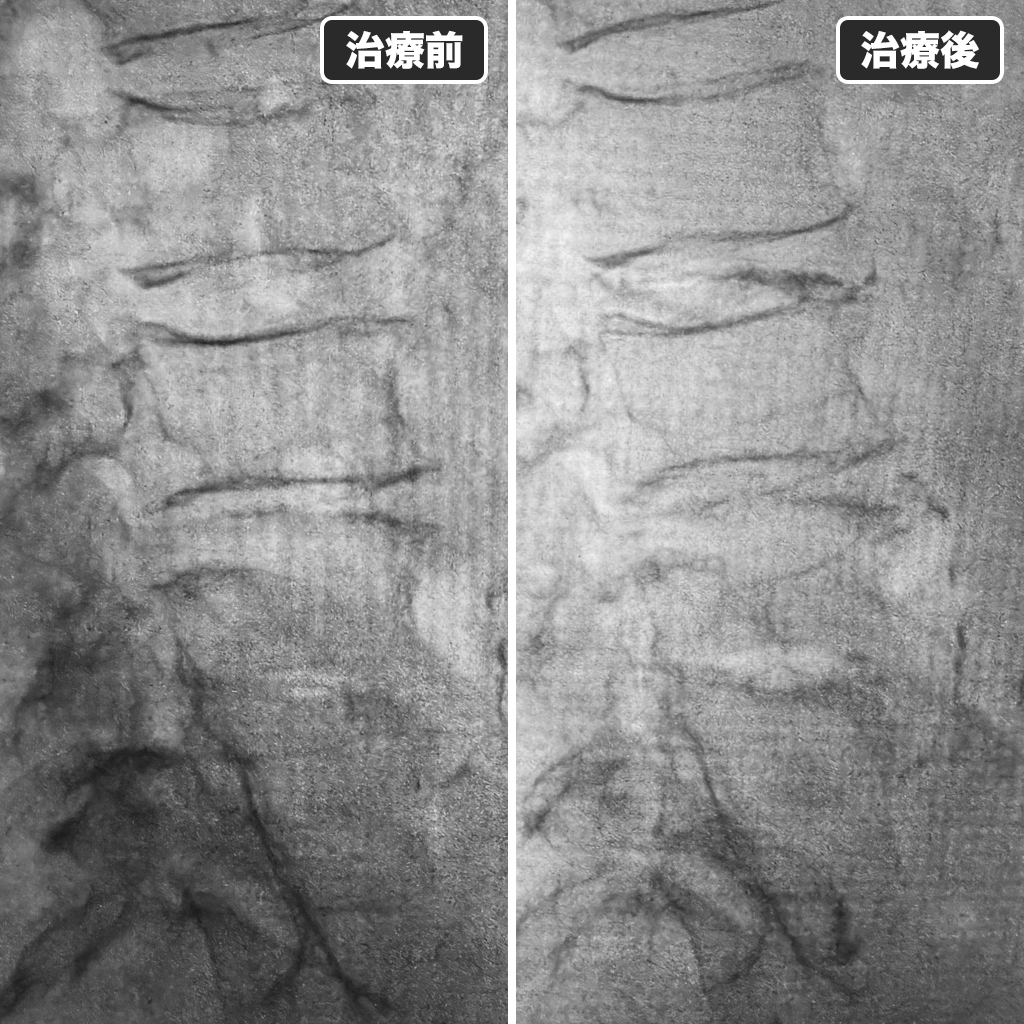

治療前後のレントゲン

治療前後のレントゲン写真になります。左側が治療前、右側が治療後になります。ラウンドされるのは1ヵ月後にしてもらうようにお願いしましたが、お返事が曖昧でしたので少し心配しております。